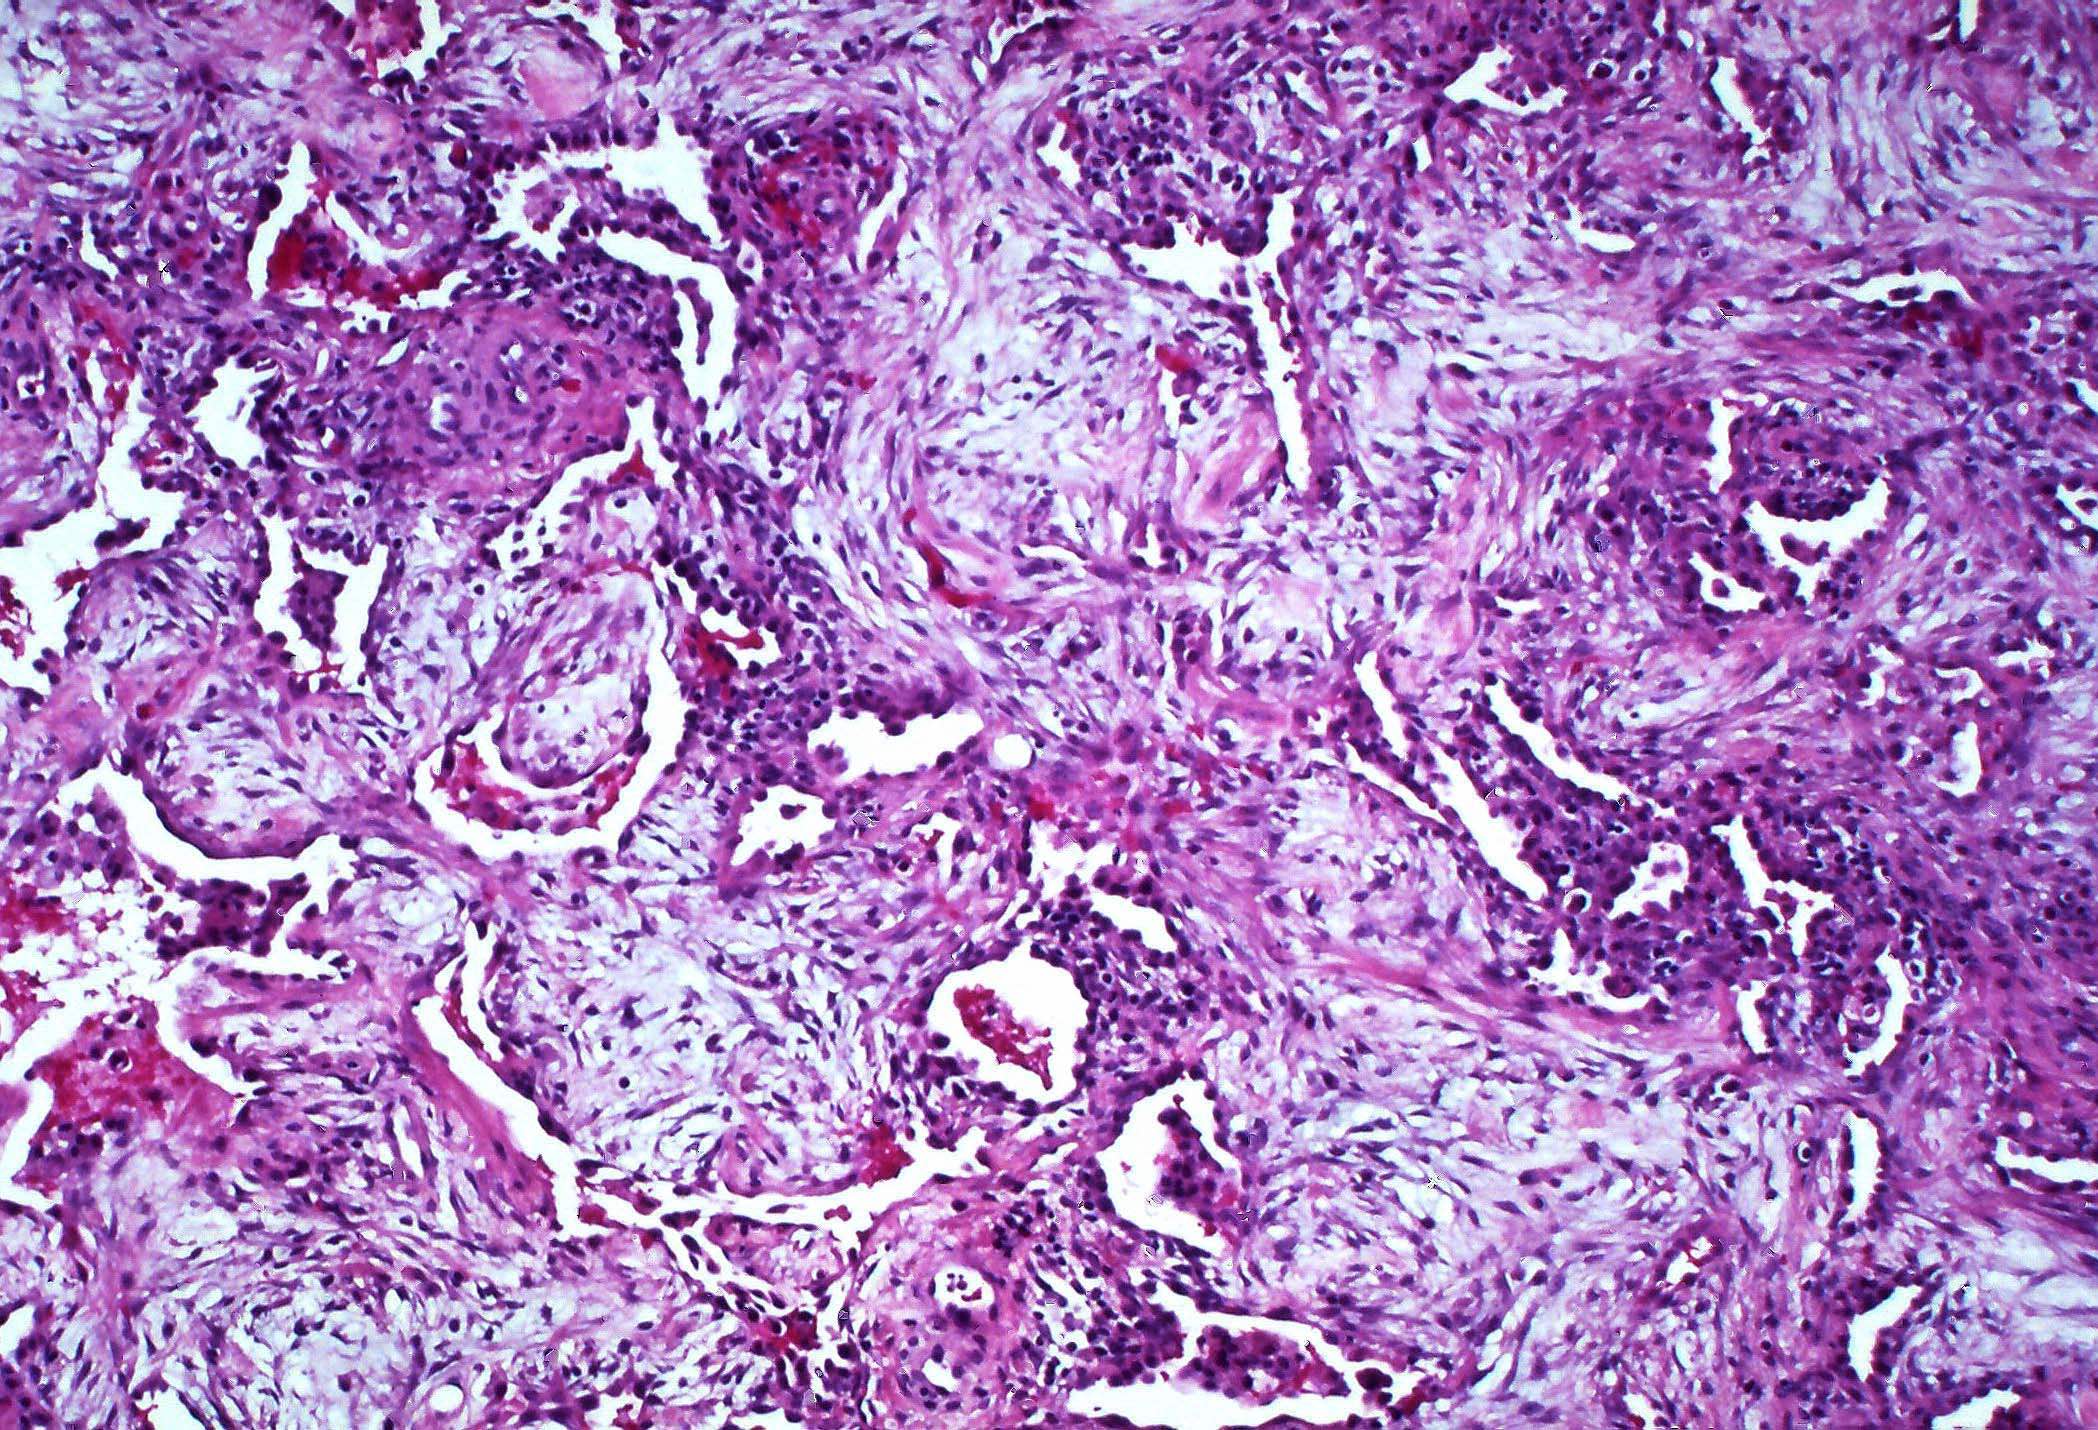

Microscopic (histologic) description

- Histopathology of DAD progresses from exudative (acute) phase through proliferative / organizing (subacute) phase to chronic fibrotic phase roughly corresponding to the period of ARDS (Am J Pathol 1976;85:209, Arch Pathol Lab Med 2010;134:719, Clin Chest Med 2000;21:435, N Engl J Med 2000;342:1334)

- Phase of the disease is almost synchronous throughout the lung

- Features of different phases may be combined in the transitional period or with repeated bouts of lung injury

- Exudative (acute) phase

- Alveolar change

- Hyaline membranes on alveolar duct or sacs

- Interstitial and intra-alveolar edema

- Collapsed alveoli

- Epithelial change

- Denudation and necrosis of type I pneumocytes

- Vascular change

- Necrosis of endothelial cells

- Neutrophil aggregation

- Microthromboemboli

- Hemorrhage

- Alveolar change

- Proliferative / organizing (subacute) phase

- Alveolar change

- Remnants of hyaline membrane with or without organization

- Interstitial and intra-alveolar proliferation of myofibroblasts

- Lymphocytic infiltration

- Epithelial change

- Proliferation / hyperplasia of type II pneumocytes

- Vascular change

- Endothelial injury and thromboemboli in arterioles

- Alveolar change

Microscopic (histologic) images

Contributed by Akira Yoshikawa, M.D. and Yale Rosen, M.D.